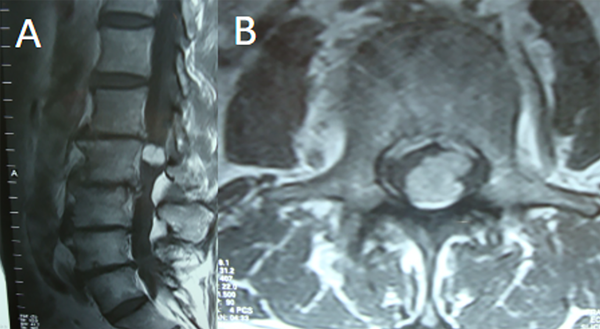

Fig 6. Caso 2. RMN: T1 con contraste sagital (A) y axial (B) que objetiva lesión nodular intradural extramedular L1-L2 a izquierda, con realce homogéneo con contraste.